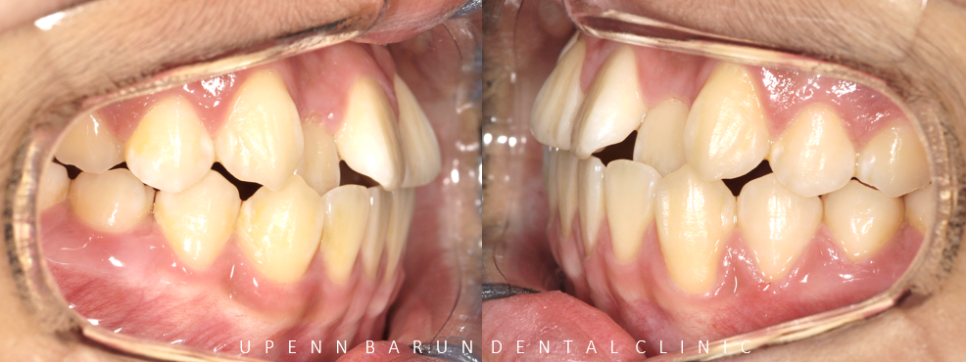

청소년 교정의 치료 전 ,후

치료기간 2021.03 ~ 2023.1

악궁확장을 통해 비발치로 교정이 마무리된 모습입니다.

위 아래의 치아가 정상적인 교합이 되었을때 음식을 씹거나 발음을 하는데 적절한 기능을 갖게 됩니다.

정상적인 교합이 이루어지지 않으면 그만큼 치아의 기능이 떨어지게 되는데

교정 후 반대교합이 개선되고, 치아끼리 맞닿는 부분도 제자리를 찾아 올바른 교합관계로 개선되었습니다.

얼굴 사진을 보시면 교정이 마무리 되고 치열이 가지런해졌을 뿐만 아니라 입술도 입체적으로 변해 스마일라인도 시원한 미소로 변화되었습니다 ^^